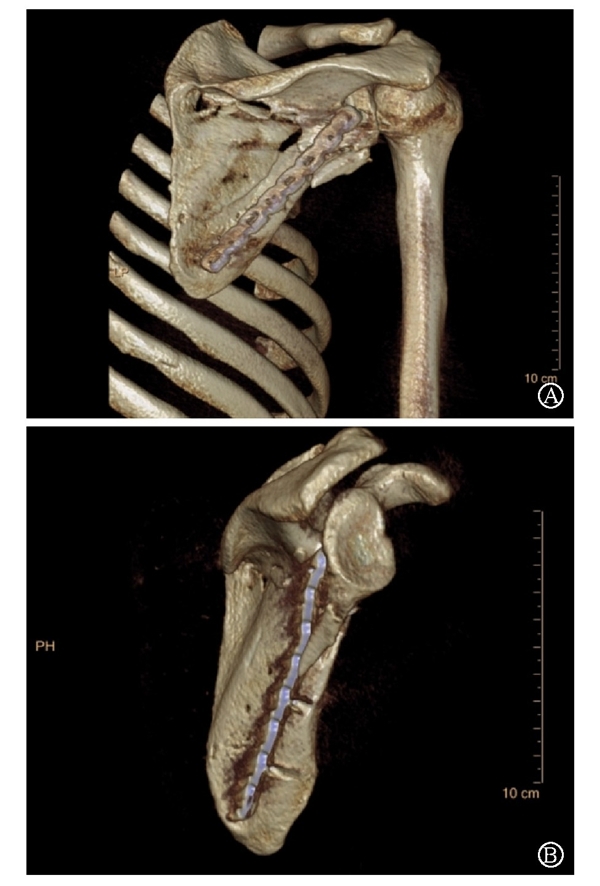

病例2为1例累及肩胛盂、肩胛颈和肩胛骨体部的复杂肩胛骨骨折(图11-12)。

术前设计采用跨骨折区域钢板螺钉固定(图13)。术中可见纵向骨折区域骨质薄弱,骨折粉碎严重,钢板放置位置有限,操作极其困难(图14)。术中采用多块接骨板跨骨折区域固定,术后X线片及三维CT重建显示复位满意(图15)。针对此病例,如果采用缝线辅助固定技术,可使手术操作过程简化,达到同样的固定效果(图16)。

图11 CT三维重建及轴位重建示肩胛骨骨折累及肩胛盂、肩胛颈和肩胛骨体部 图A:CT三维重建;图B:CT轴位重建